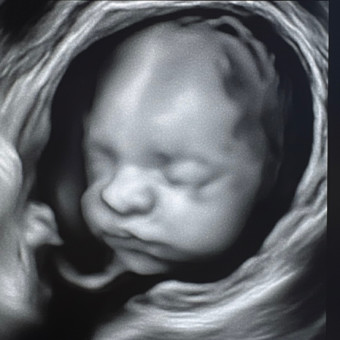

Kenya's Baby Registry

Kenya Ochoa & Abraham Ochoa

Casa Grande, AZ

January 2026